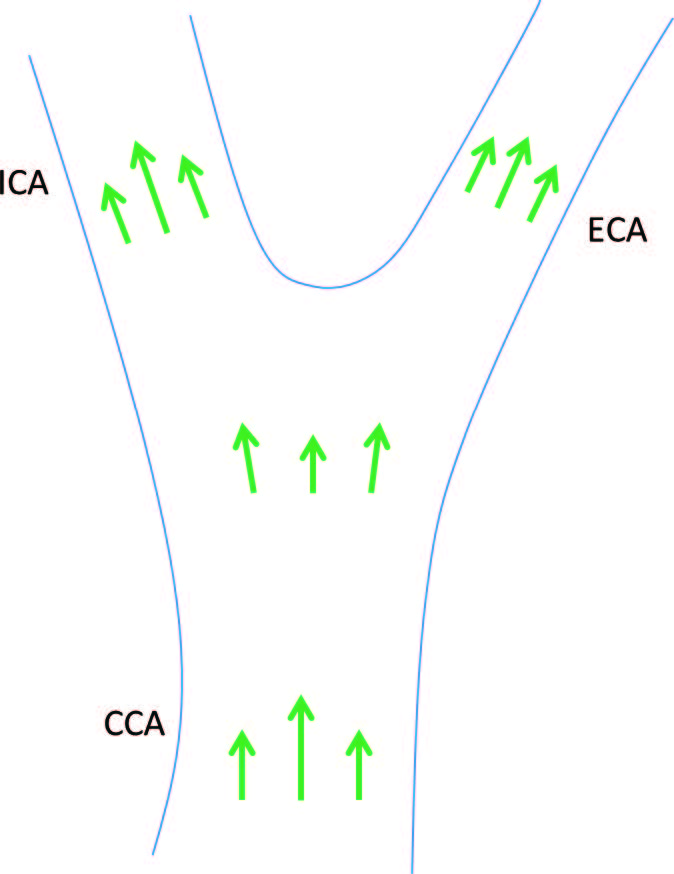

Режим цветового допплеровского картирования (ЦДК) критически важен в современной ультразвуковой диагностике. Скорость кровотока рассчитывается методом автокорреляции данных акустического сигнала, используя специфическое фильтрование принимаемых сигналов. Данные о скорости частиц относительно направления распространения ультразвуковых лучей обрабатываются ультразвуковой системой для обнаружения ламинарного потока крови. Типичным примером является кровоток в сонной артерии – максимальная скорость может быть рассчитана путем коррекции угла к полученным данным. Данные о максимальной скорости кровотока в момент систолы широко используют для диагностики и поиска артериальных бляшек.

Однако сердечно-сосудистая система человека насыщена сложными участками, где кровоток принимает не только ламинарную форму. Например, в случае исследований при бифуркации и образовании вихревых токов крови. Такие сложные потоки не могут быть определены с помощью традиционного режима ЦДК, поскольку он измеряет одномерную скорость в сосудистом русле. Более того, зачастую режим ЦДК может регистрировать аномальные изменения параметров скорости ламинарного кровотока только в случаях значительного перекрытия русла сосуда бляшкой. Для исследования кровотока в искривленных сосудах и патологических случаях требуется новый метод, способный регистрировать мельчайшие изменения скорости направления движений частиц крови по сосуду с учетом всех анатомических особенностей его русла.

Для того чтобы получить направленный вектор скорости кровотока в любой его точке используются множество разнонаправленных циклов приема-передачи эхосигнала (Рисунок 2). Затем скорость (величина вектора скорости) рассчитывается с помощью метода, изображенного на рисунке 3. Благодаря множественному разнонаправленному сканированию, в каждой исследуемой точке кровотока ультразвуковая система получает вектора скорости в плоскости каждой итерации цикла приема-передачи эхосигнала. Истинный вектор скорости вычисляется путем компаундинга и регрессионного анализа полученных данных. Кроме того, поскольку платформа ZST+ хранит дамп оригинального эхосигнала, то он же используется для формирования изображения в B-режиме, что делает возможным как высокочувствительную регистрацию потока, так и высокое разрешение серошкального изображения.